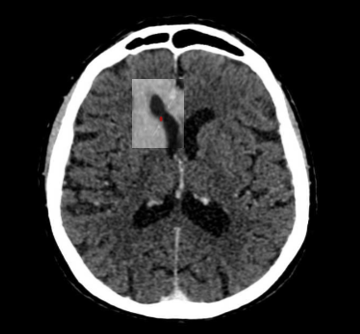

Medios de contraste

Se pueden apreciar imágenes que pueden confundirse con aneurismas o malformaciones vasculares, pero al detallarse en otro plano (coronal), las  identificamos como  variantes anatómicas como elongaciones, bifurcaciones ,  anomalías venosas del desarrollo o vasos tentoriales.

Fig. 11.